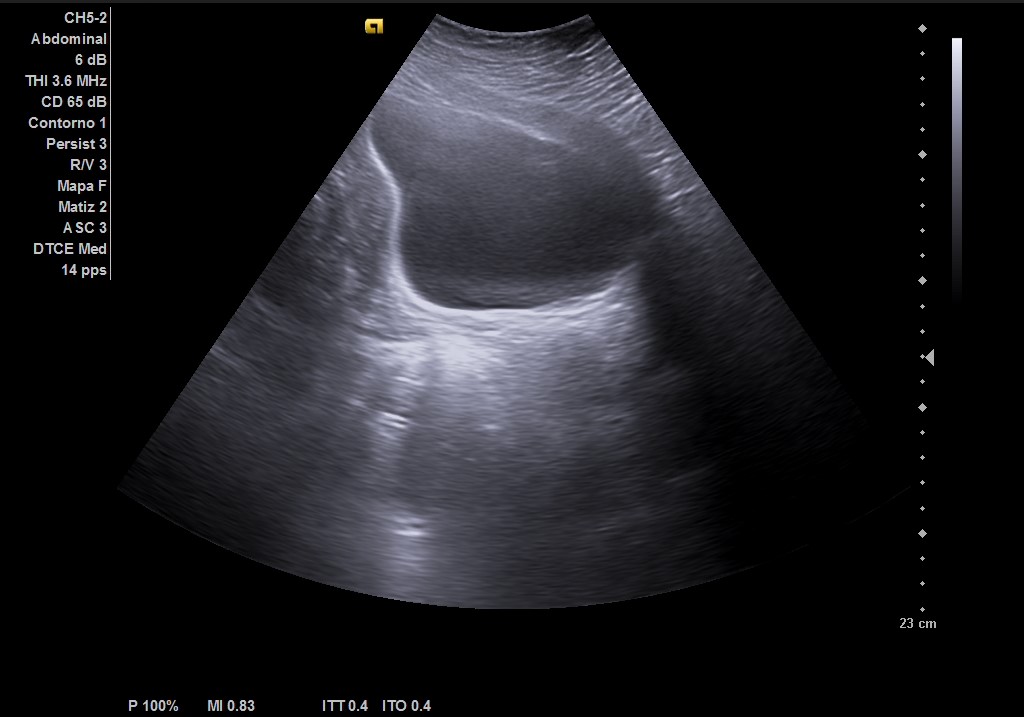

Ecografía abdominal: masa heterogénea de 10 x 10 cm dependiente de útero con vascularización periférica. No se observa la vejiga al estar repleccionada y desplazada por dicha masa. Se vuelve a hacer ecografía con vejiga llena y se observa cómo deforma la pared por efecto masa. Vejiga sin litiasis en su interior, no globo vesical.

Metrorragia secundaria a mioma uterino de gran tamaño.

La paciente es valorada en consulta de patología ginecológica. Le realizan una ecografía abdominal y transvaginal que describe: útero de unos 13 cm de histerectomía. Presenta varios miomas intramurales, destacando uno en cara posterior de 110 x 102 mm que parece contactar con cavidad endometrial sin desplazarla.